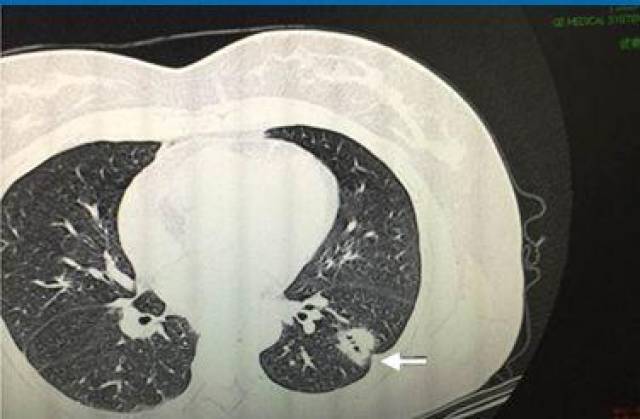

【病例讨论】双肺弥漫囊状空泡(有图)请教各位专家 [病例帖]